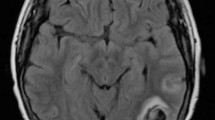

From June 2017 to June 2023, 38 inpatients diagnosed with CVT were prospectively enrolled consecutively at the Department of Neurology, Peking Union Medical College Hospital (PUMCH). In the study, CVT was diagnosed according to established criteria and confirmed by at least one of the following neuroradiological examinations: computed tomography venography (CTV), magnetic resonance imaging (MRI), magnetic resonance venography (MRV), or digital subtraction angiography (DSA) [12]. Demographic characteristics, medical history, clinical manifestations, laboratory tests, imaging data (CT, MRI, MRV, DSA), and treatment were collected. Laboratory results including thrombophilia tests such as PC, PS, ATIII and activated PC resistance (APC-R), antiphospholipid antibodies (aPL) such as anticardiolipin antibodies (aCL), anti-β2-glycoprotein I antibodies (aB2GPI), lupus anticoagulant, and antinuclear antibodies, and homocysteine. All 38 patients signed informed consent forms for enrollment, and whole blood samples were collected for WES. Severity of illness at admission and discharge was assessed by modified Rankin Scale (mRS) [13].

Table 1 presented the demographic, clinical, and imaging characteristics of 38 CVT patients. The average age was 39.61 ± 17.20 years, with 20 females and 18 males. Headache was the most common symptom (76.3%), followed by visual disturbances (34.2%), focal neurological deficits (34.2%), altered consciousness (31.6%), seizures (21.1%), and cognitive impairment (21.1%). Tinnitus and abnormal mental behavior were also reported by some patients. The most frequently involved venous sinus was the transverse sinus (57.9%), followed by the sigmoid sinus (55.3%) and the superior sagittal sinus (42.1%). Cortical vein thrombosis was observed in nine patients (23.7%). Additionally, 6 patients (18.4%) had cerebral deep venous thrombosis involving Gallen vein or internal cerebral veins. Approximately 70% of patients had multiple venous sinuses involvement. Eighteen patients presented with hemorrhage, and 21 patients presented with brain swelling and focal edema. Except for 2 patients who died and 1 patient whose condition remained poor, 92.1% of the patient’s showed improvement at discharge. The median mRS at admission was 2, whereas the median mRS at discharge was 1.